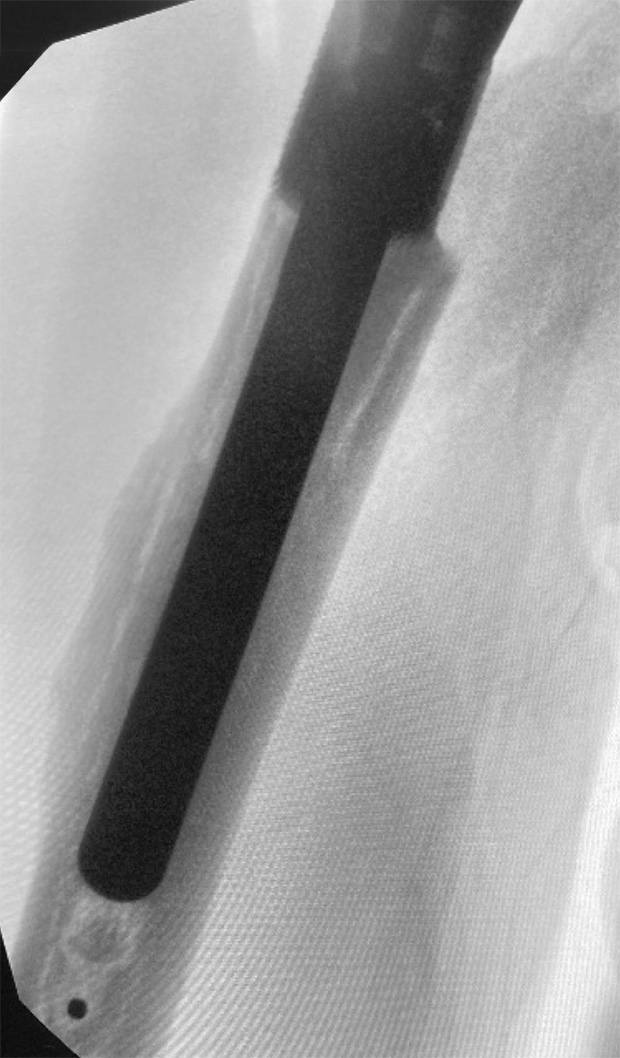

Post-op

- Pictures 12 and 13: post op x-rays with MEGA C Upper Limb and LINK Embrace components

- Distal Stem, cemented and well fixed